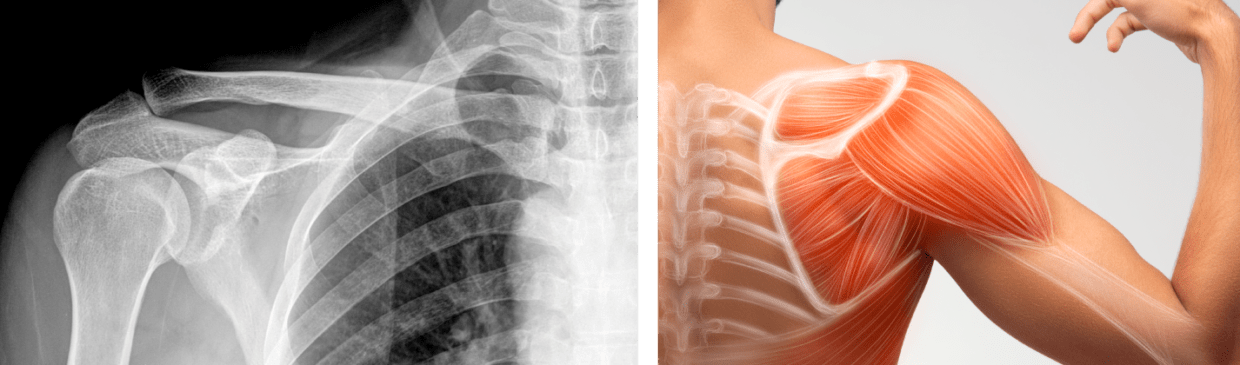

La Paz, 13 de ene 2026 (ATB Digital) .- El traumatólogo Abraham Sulcata explicó que la calcificación es la acumulación de cristales de calcio en los tendones del hombro, provocando un dolor agudo en la zona. Esta afección, según Sulcata, aparece por la mala postura o realizar movimientos repetitivos que afecten directamente a los hombros.